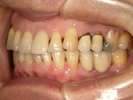

50代女性

![]() |

治療前 |

治療中。仮歯。 左上の奥にインプラント埋入。 噛みあわせ治療を行いました |

治療後 全体の歯で食事がおいしくできるようになったと喜んでおられました。 |